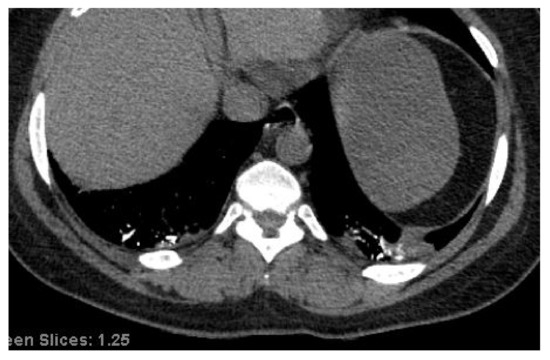

4.1. Endothelial Dysfunction